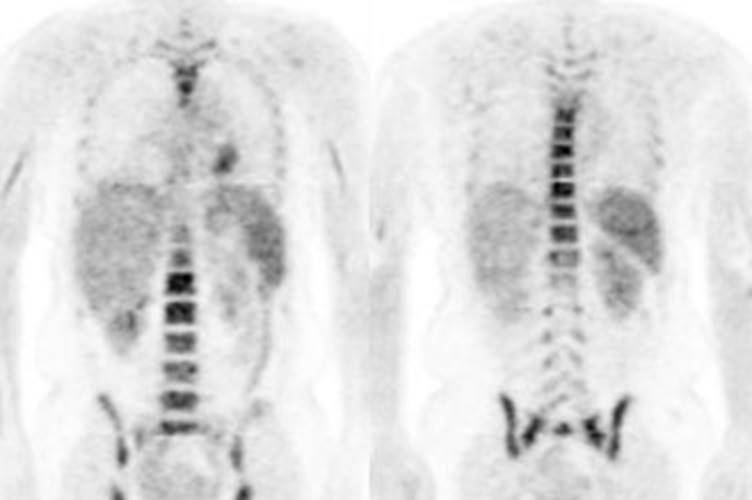

Figure 22 - Growth colony effect: The patient shown below

had received growth colony stimulating factor (GCSF). Note the extensive

increased marrow activity. Note increased splenic activity also seen as a result of GCSF therapy.

o

�Treatment

with granulocyte stimulating factors can also produce diffuse skeletal

FDG accumulation [9] which can interfere with accurate PET imaging